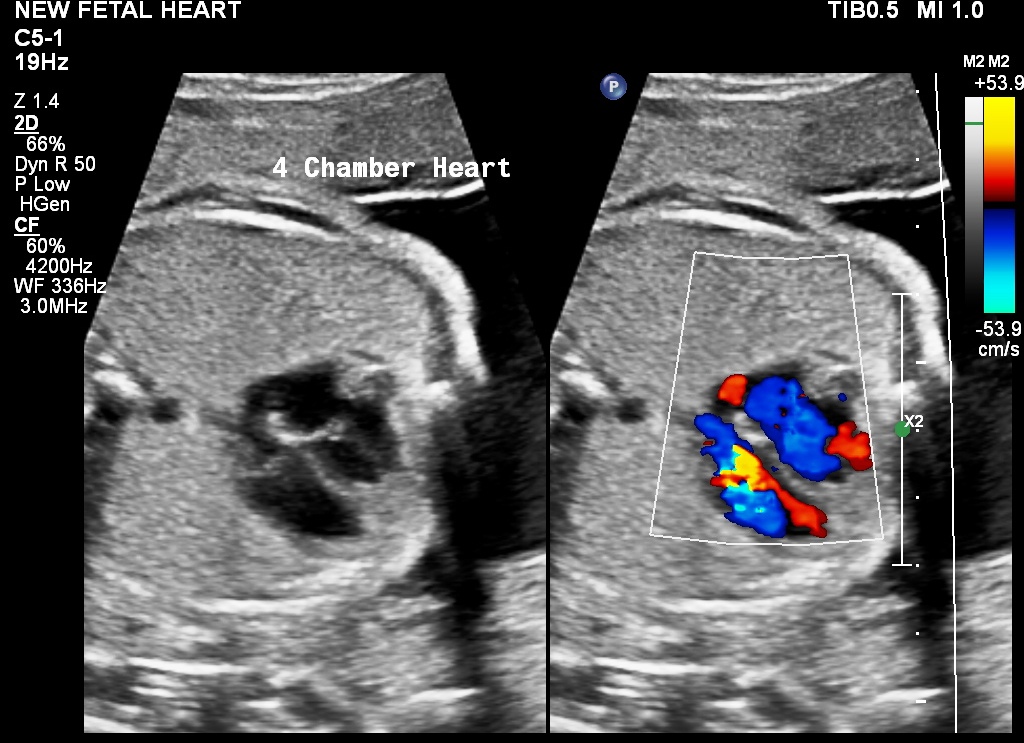

Sonography in the later part of pregnancy gives information on the fetal weight and whether the fetal weight is within normal limits. It is also done to estimate the quantity of liquor. Low position of the placenta can be detected. Some anomalies which become apparent only later in pregnancy may be detected. Findings on this scan help the obstetrician take decisions regarding the pregnancy.